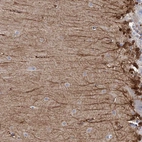

Immunohistochemical staining of human cerebellum shows strong cytoplasmic positivity in molecular layer cells.